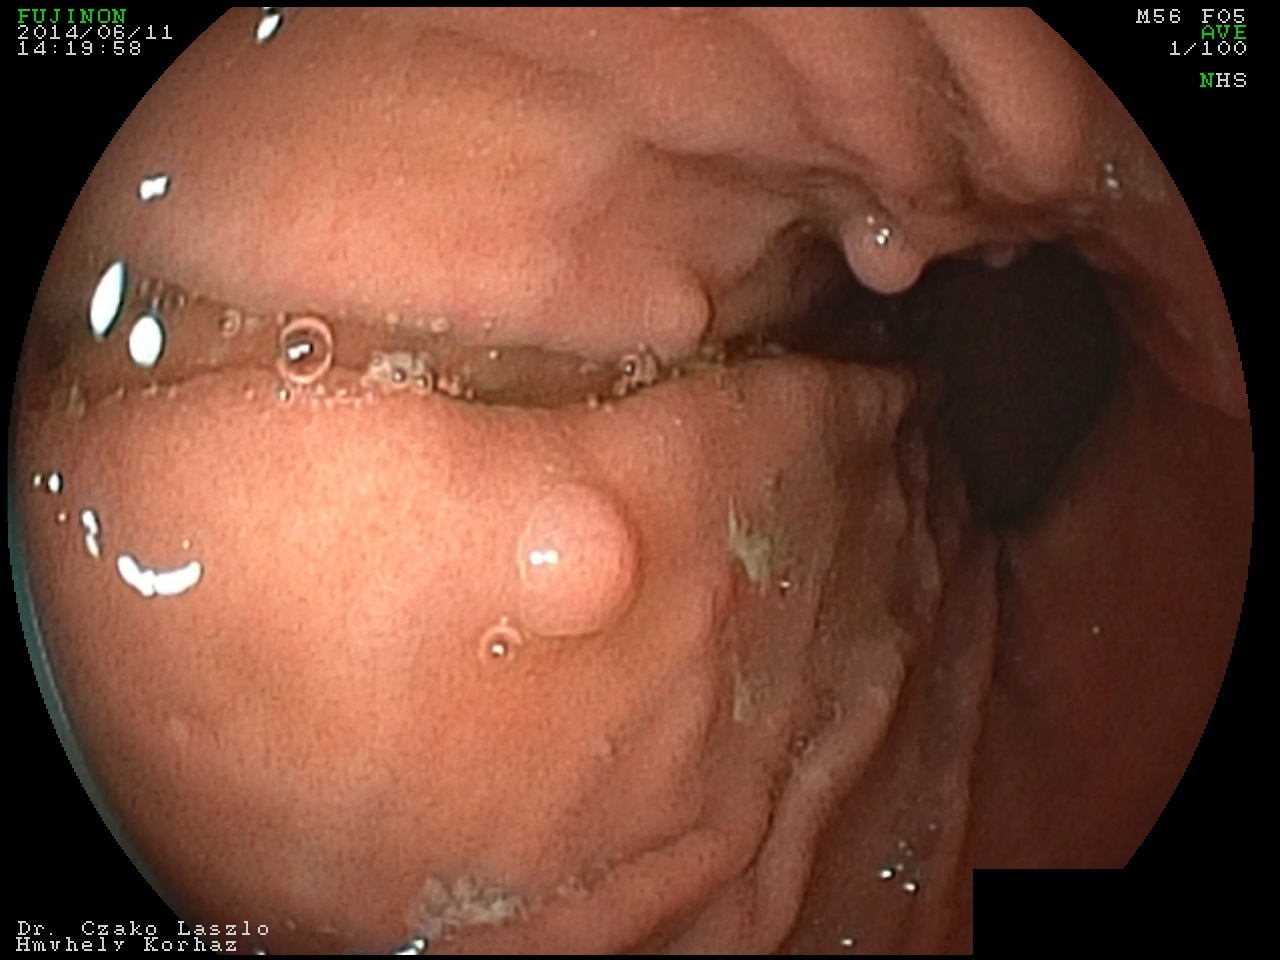

Fundusmirigy polypok

Dr. Czakó László